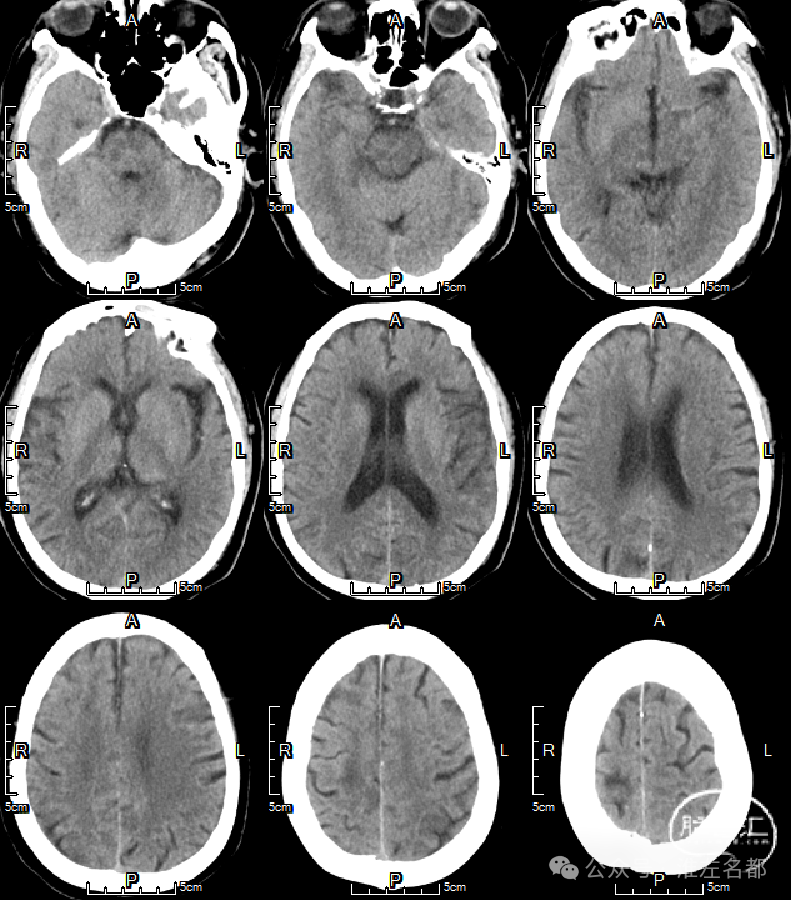

2024-01-14 08:36

复查多模式CT

CT平扫:双侧胼体膝部和右侧额顶叶皮质多发梗死低密度影。

CTA:右侧大脑前动脉原A2段狭窄位置管腔闭塞。

脑CTP:右侧大脑前动脉供血区较大范围TTP显著延长。